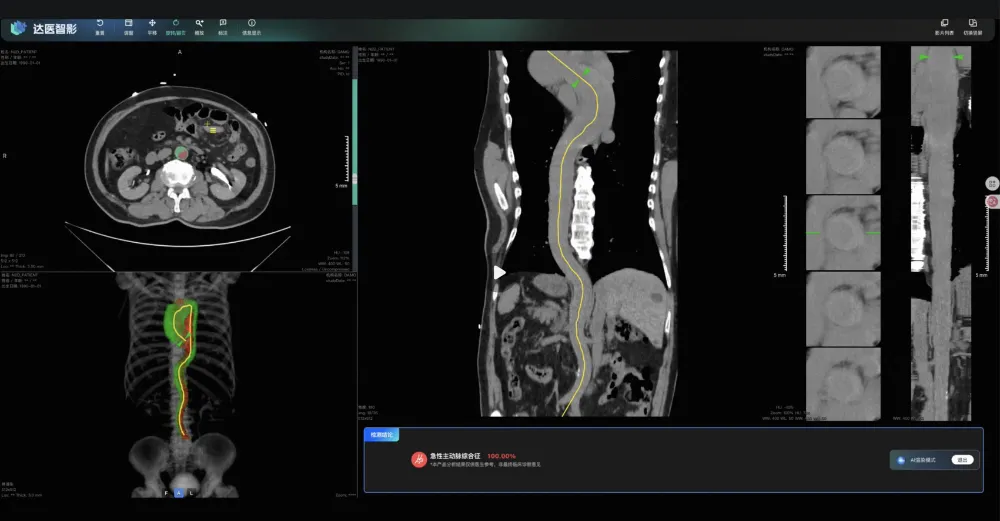

經過三年多的碰撞、爭吵和調整,一個名為“ iAorta ”的模型終於誕生了。和之前的癌症篩查模型一樣,今年8月份,這個研究也登上了 nature medicine。

在論文中,科學家們回顧了之前的13萬名急診胸痛患者,裏面有121名主動脈綜合徵患者在初診時都被遺漏。但當醫生們把當時這些患者的平掃CT交給 iAorta 後,其中109人被確診了,漏診率從觸目驚心的48.8%,驟降到4.8%!

和腫瘤醫院一樣,浙大一院等試點醫院的醫生們,會在患者拍完CT後,都放進AI模型裏跑一遍篩查,在後台默默地盯着每一張片子。

就在前段時間,上海一家試點醫院的胸痛中心,短短兩個月裏,iAorta就從15584名患者中,精準地揪出了21個主動脈夾層患者,敏感性達到95.5%,特異性達到99.4%。

這21名被AI找回來的患者,平均確診時間,縮短到了驚人的1.7小時。每提前一個小時,就意味着為生命爭取了1%-2%的生機。

其中有一個43歲的大哥,上腹部疼了12個小時才來醫院,醫生初步懷疑是膽結石,就開了個上腹部平掃CT。檢查剛做完,結果還沒到醫生手裏,iAorta就彈出了紅色警報,接診醫生立刻安排了增強CTA,最終確診為主動脈夾層。

從入院到確診,全程只用了94分鐘。

如果沒有這個AI,這位大哥很可能會在膽結石的診療路徑上越走越遠,而他身體裏的那顆炸彈,隨時可能引爆。是AI,硬生生把他從死神的賽道上拽了回來,也拯救了他背後的一整個家庭。